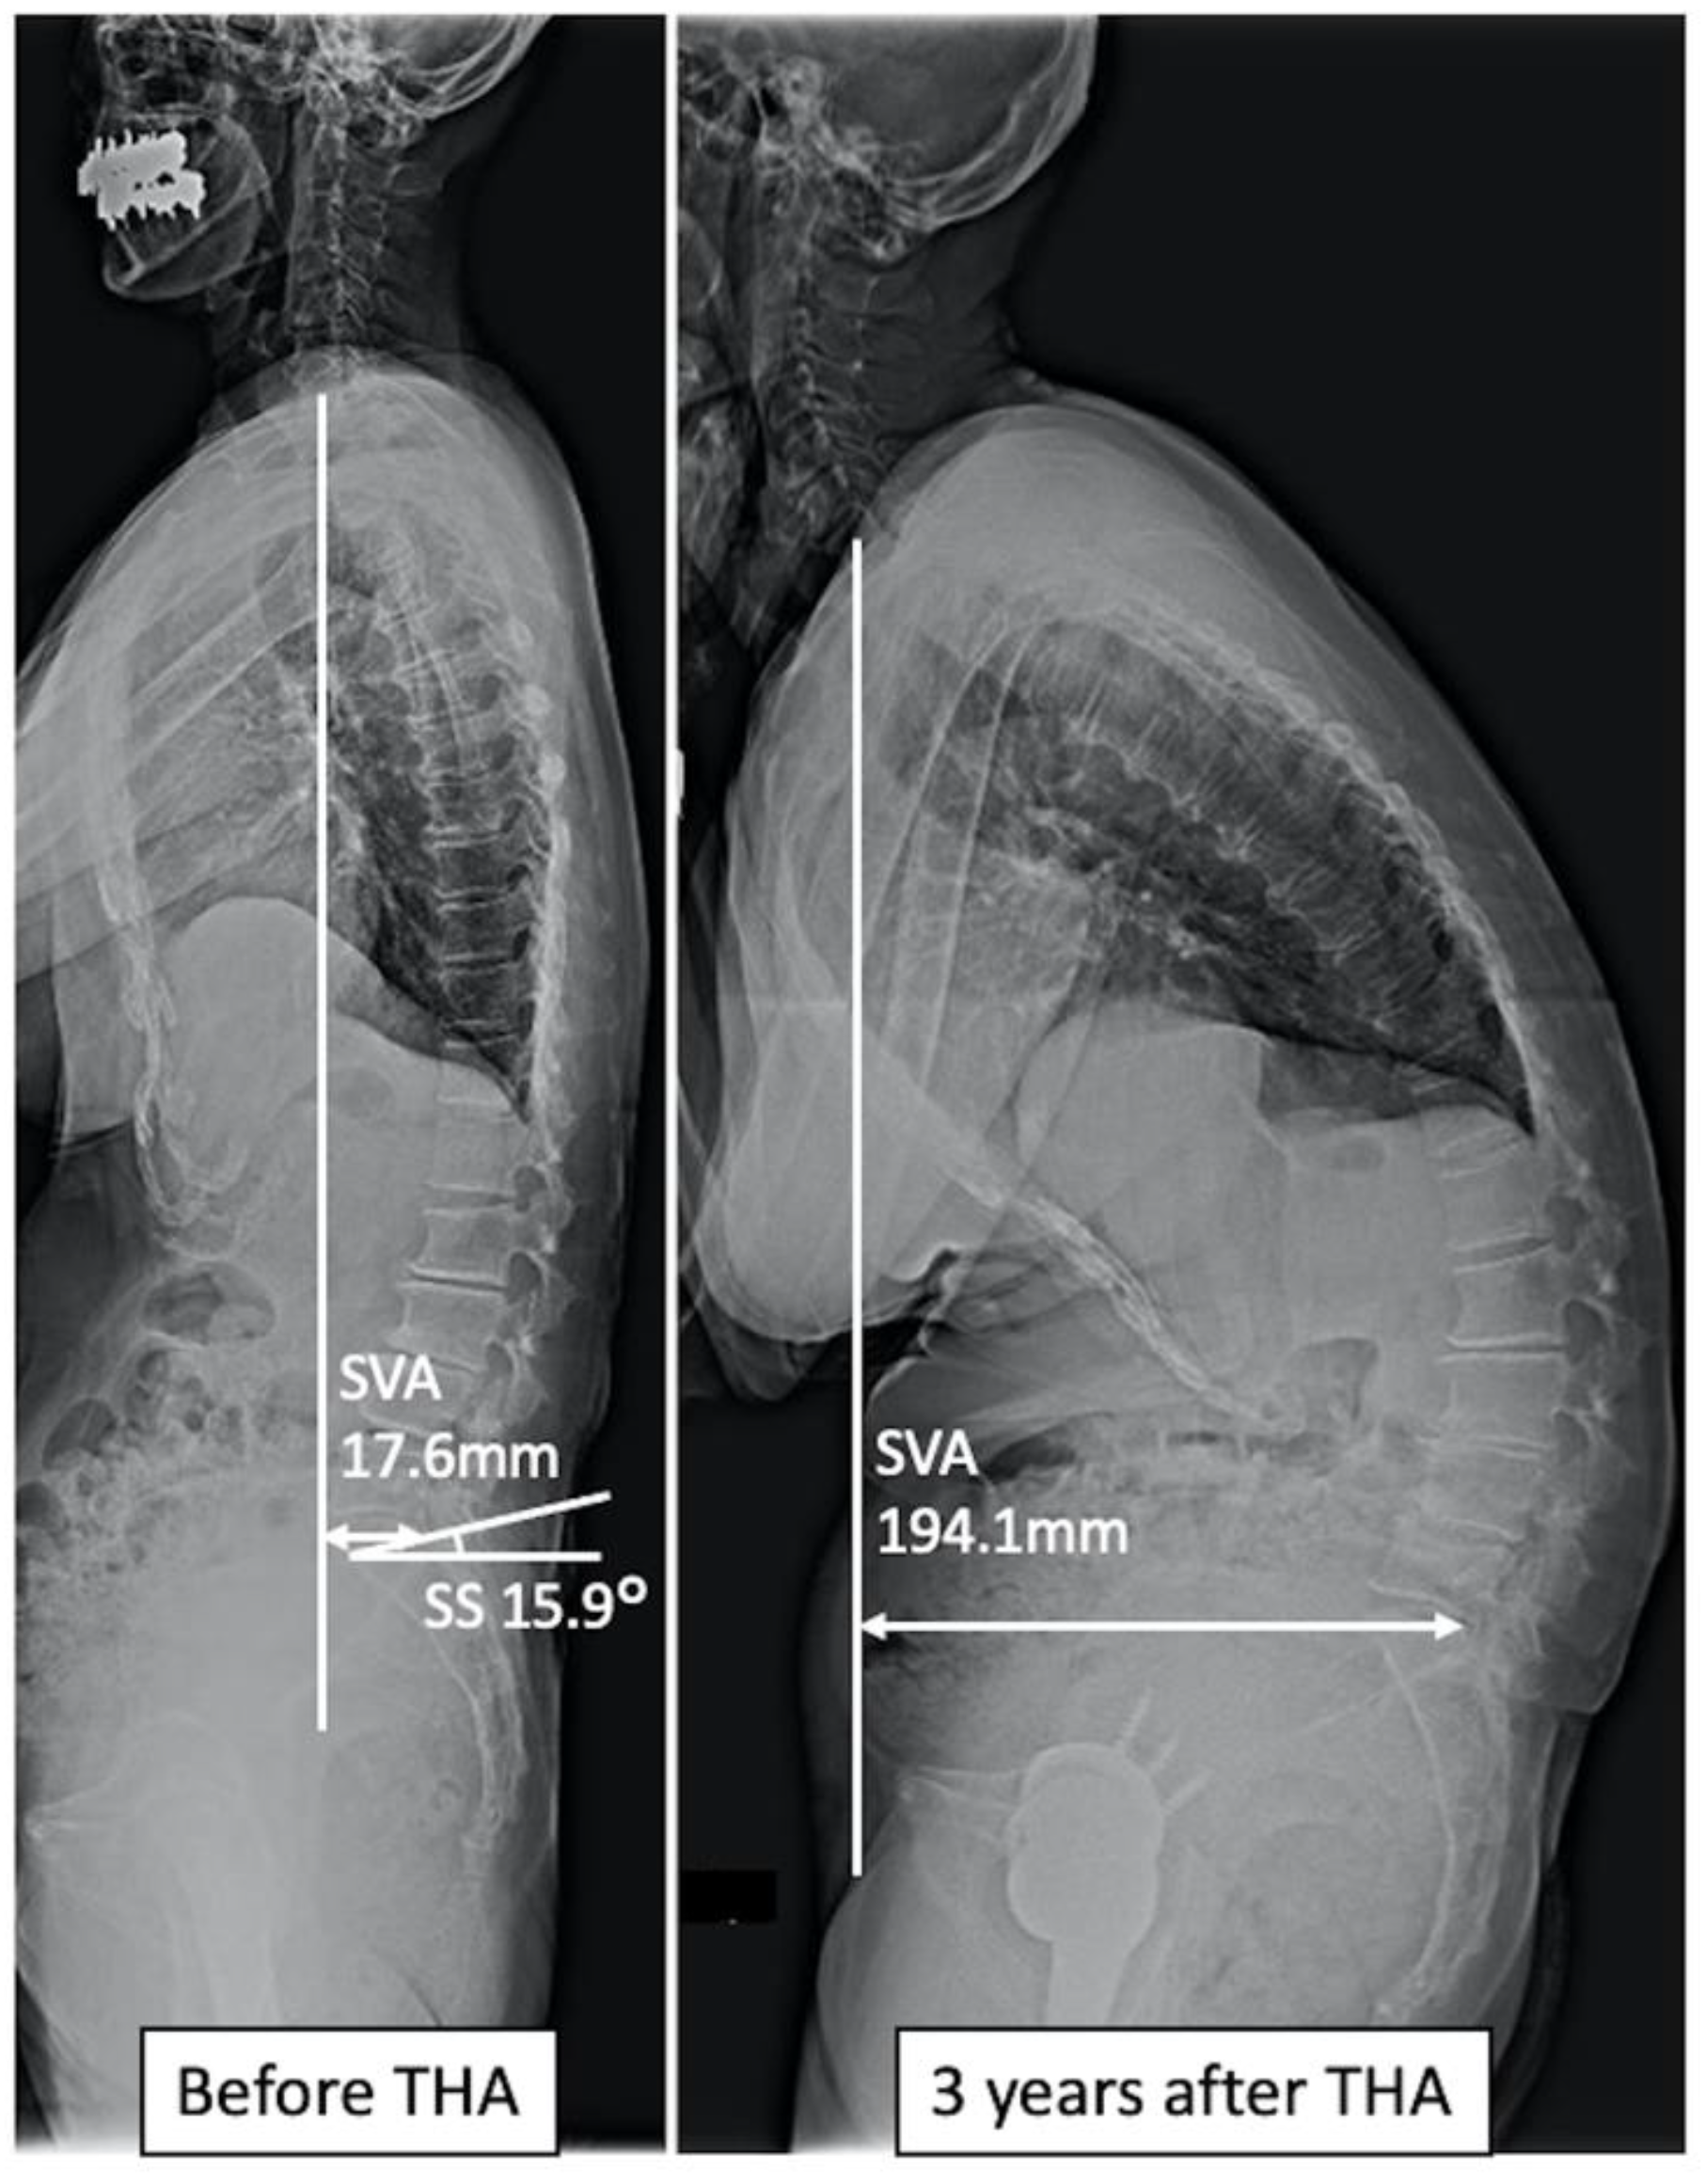

| SVA (mm), mean ± SD | 47.9 ± 26.1 | 45.3 ± 47.2 | 0.665 |

| SS (degrees), mean ± SD | 32.7 ± 10.2 | 42.7 ± 12.4 | 0.006 |